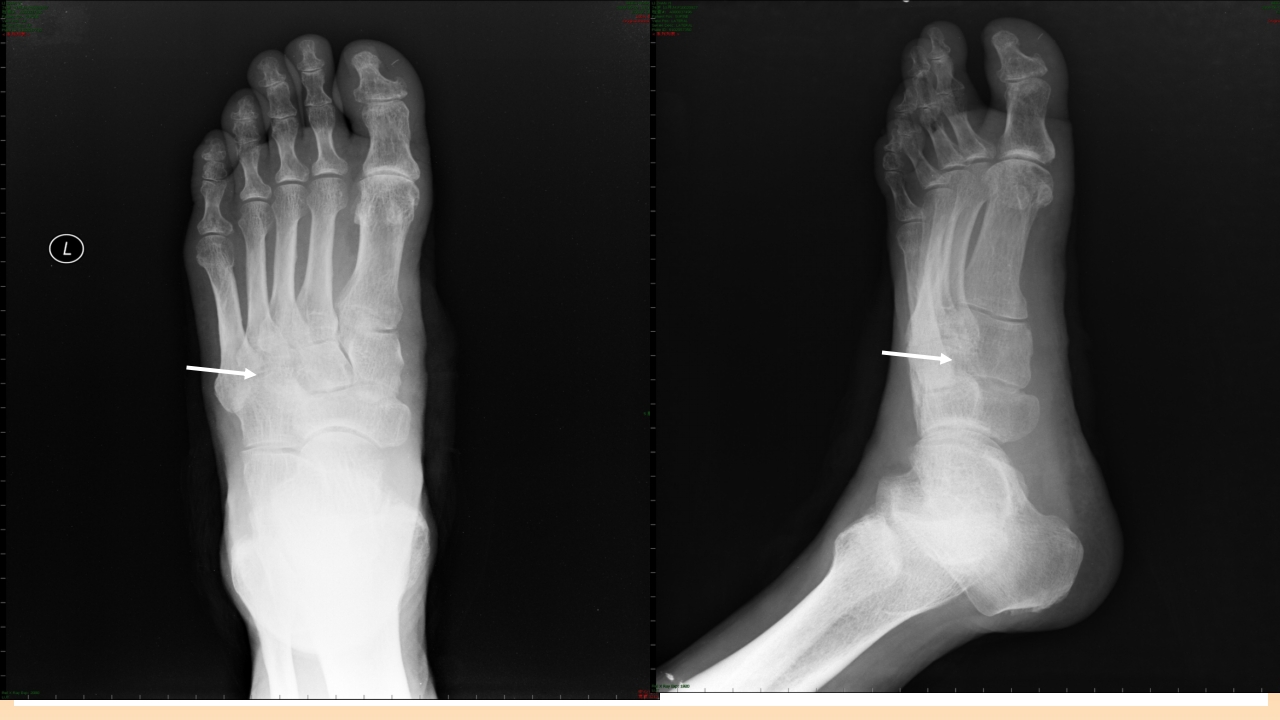

糖尿病足的治疗与护理 目录/content 一 糖尿病足的定义 二 糖尿病足发病机制及诊断? 三 糖尿病足如何治疗? 四 如何预防和护理糖尿尿足? 1 糖尿病足的定义 糖尿病足定义 糖尿病足:主要是与糖尿病下肢远端神经异常和不同程度的外 周血管病变相关的足部感染、溃疡和(或)深层组织破坏。 由于神经营养不良和外伤的共同作用,可引起Charot关节。 是糖尿病最严重的和治疗费用最高的慢性并发症之一。 糖尿病足流行病学资料 国外资料显示: 在所有因糖尿病住院的有关问题中,糖尿病足占到47%。 5%-10%糖尿病患者有不同程度足溃疡,1%的糖尿病患者截 肢。 糖尿病足是许多国家截肢首位原因。 中国糖尿病防治指南,2005,55 糖尿病足流行病学资料 在我国糖尿病足患病率占糖尿病患者的14%, ...